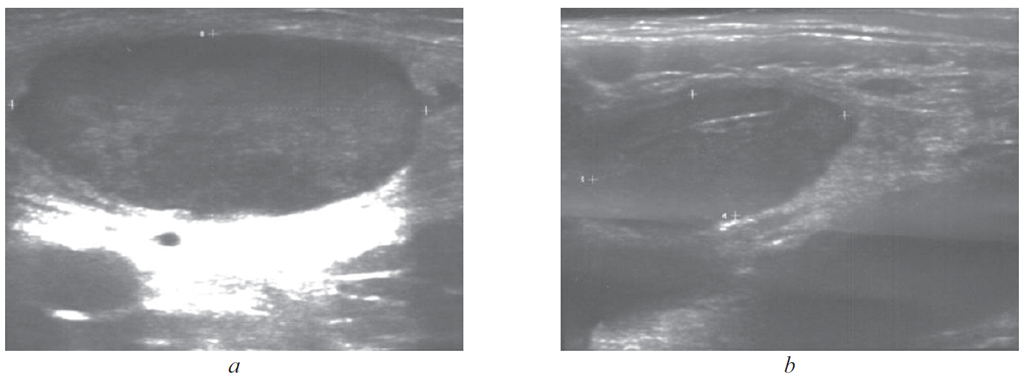

Tularemia is an acute zoonotic natural focal disease caused by Francisella tularensis, with a variety of pathogen transmission mechanisms. A person becomes infected in various ways, mainly through insect bites (mosquitoes, ticks), through direct contact with infected animals, and also by inhalation. The disease is characterized by high fever, intoxication, inflammatory changes in the area of the entrance gate, regional lymphadenitis. It is often difficult to suspect tularemia in the early stages due to the lack of specificity of clinical manifestations (fever, intoxication, regional lymphadenitis). Even in endemic regions, in most cases, acute respiratory viral infection, lymphadenitis, fever of unknown origin are diagnosed, which leads to a late start of etiotropic treatment. There is a clinical case of tularemia in a 13-year-old child who was misdiagnosed in the early stages of the disease. And only a careful collection of an epidemiological history (stay in an endemic area, a mosquito bite), as well as a competent assessment of clinical and laboratory data, allowed tularemia to be included in the differential diagnosis on the 18th day of the disease and confirmed by the detection of the highest titers of anti-tularemia antibodies in blood serum. Thus, against the background of low morbidity, especially in childhood, there is no alertness among doctors of all specialties, which leads to late diagnosis and, as a consequence, late started specific treatment. All children with prolonged fever in the presence of lymphadenitis of unknown genesis, who have been in a territory unfavorable for tularemia, need to undergo a specific examination to identify mild and erased forms of the disease.